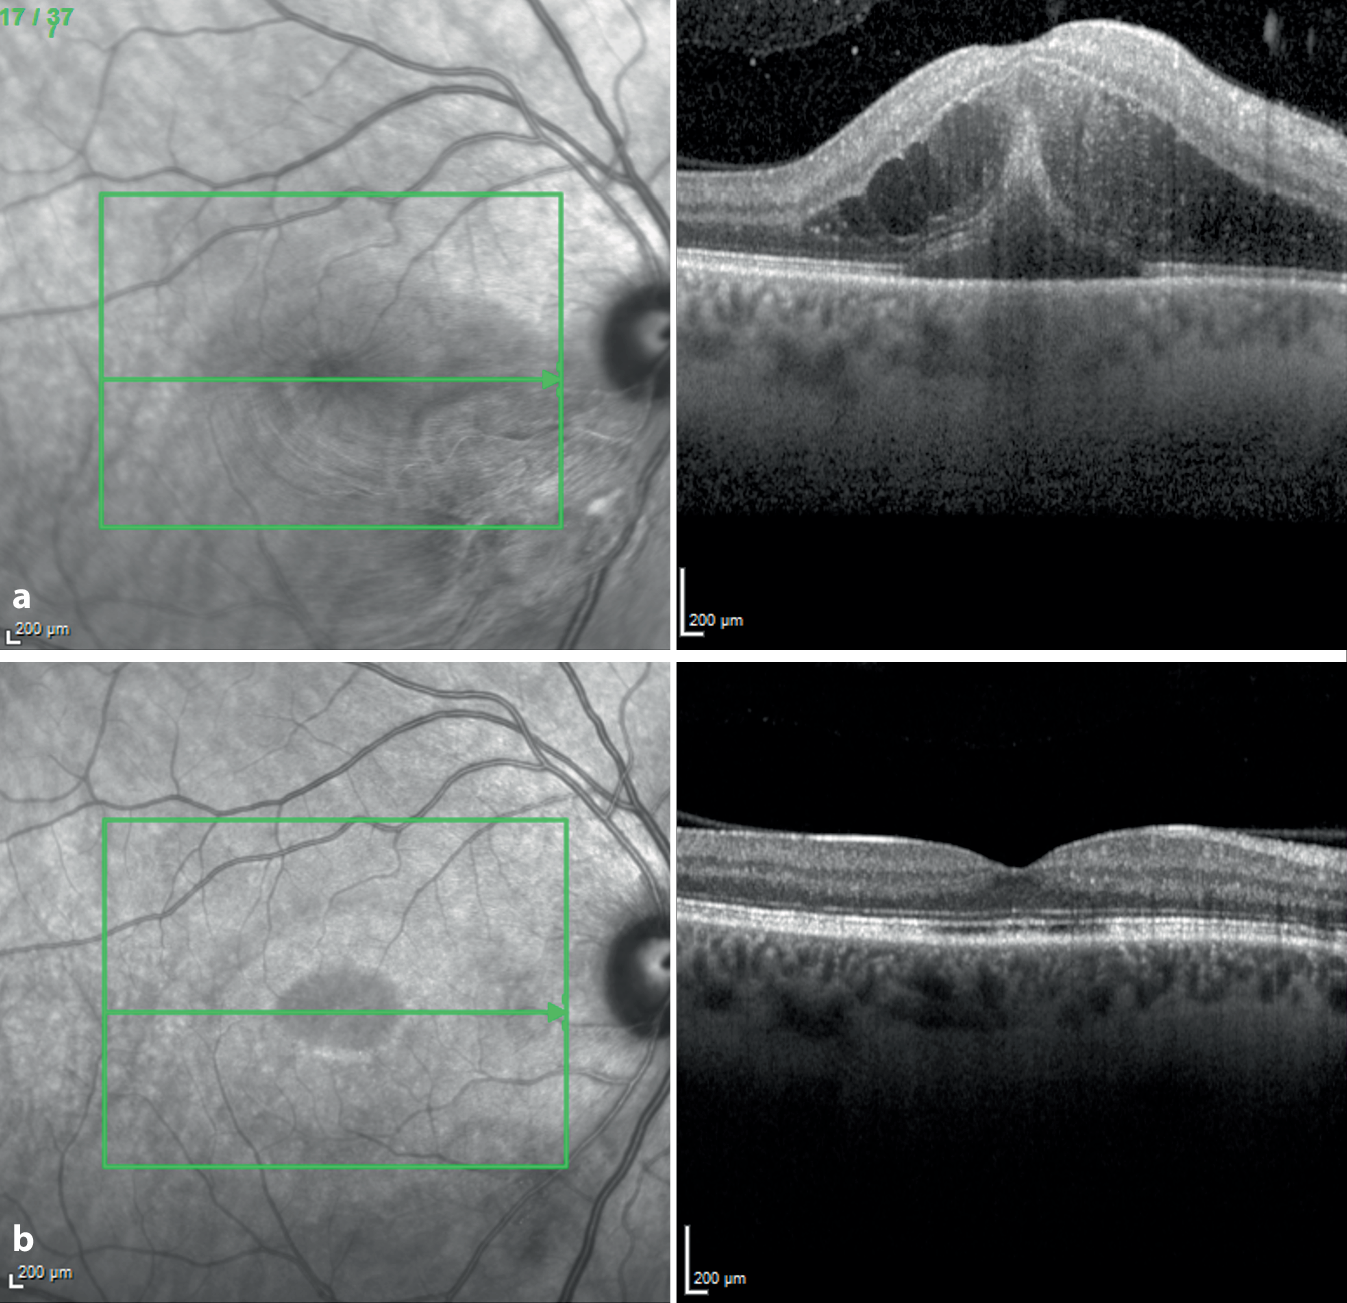

Am rechten Auge war die Sehschärfe (mit Korrektur) auf 1/20 Metervisus reduziert, während der bestkorrigierte Dezimalvisus links bei 1,2 lag. Der Augendruck lag bei rechts bei 11 und links bei 20 mm Hg. In der Spaltlampenbiomikroskopie zeigte sich an beiden Augen ein reizfreier Befund. Fundoskopisch fiel am rechten Auge eine etwa 1,5 Papillendurchmesser große weißliche und unscharf begrenzte perivaskuläre retinale Läsion im Bereich des unteren temporalen Gefäßbogens auf (Abb. 1). In der optischen Kohärenztomographie (OCT) zeigte sich dort eine deutliche Verdickung der Nervenfaser- und inneren Netzhautschichten sowie makuläre intra- und subretinale Flüssigkeit (Abb. 2a). In der Fluoreszenzangiographie zeigten sich in der Spätphase perifokale Leckagen sowie Hinweise auf eine begleitende Vaskulitis (Abb. 3).

Abb. 2

OCT-Aufnahme der Makula des rechten Auges. a Sub- und intraretinale Flüssigkeit bei Erstvorstellung; b 6 Wochen nach Erstvorstellung zeigt sich ein trockener Befund

Am siebten stationären Tag zeigte sich bereits ein deutlicher Rückgang der Netzhautläsion sowie des Makulaödems, der bestkorrigierte Visus betrug zu diesem Zeitpunkt 0,1. Wir erhielten nun die Information, dass ein positiver Serologiebefund für Rickettsia-rickettsii-IgM und -IgG vorlag. Den Befund ließen wir uns durch eine externe Mitbeurteilung im Nationalen Referenzzentrum für tropische Infektionserreger (Bernhard-Nocht-Institut, Hamburg, Deutschland) bestätigen. Die weiteren infektiologischen Laboruntersuchungen zeigten sich unauffällig. Nach erneuter Konsultation der infektiologischen Kollegen initiierten wir eine orale Therapie mit Doxycyclin 100 mg zweimal täglich über 14 Tage, welche wir nach Entlassung des Patienten größtenteils ambulant durchführten. Parallel reduzierten wir die oralen Steroidtherapie schrittweise und vereinbarten wöchentliche Verlaufskontrollen. Zum Zeitpunkt 6 Wochen nach der Erstvorstellung zeigte sich die entzündliche Läsion fundoskisch fast vollständig (Abb. 4), das Makulaödem sogar vollständig zurückgebildet (Abb. 2b). Der bestkorrigierte Dezimalvisus lag bei 1,0, und der Patient gab eine deutliche Verbesserung des Sehens an. Eine etwa drei Monate nach der primären Infektion durchgeführte serologische Verlaufsuntersuchung zeigte negative Antikörpernachweise für R. rickettsii bei positivem IgG für die Rickettsienspezies R. africae und R. conorii.